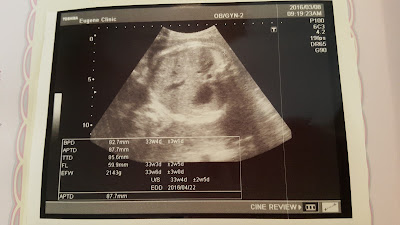

2個星期一次的產檢,覺得時間過很快

明明才剛檢查過,沒幾天又要做檢查了

下一次也是2個星期後,接下來就是週週檢查了!

今天很快速的在還沒十點就已經吃完早餐、做完產檢回到家

現在立馬把記錄文寫出來!

大肚孕人來到孕期的31w,很快就要32w了

時間咻咻咻~就快要跟Haru見面了!